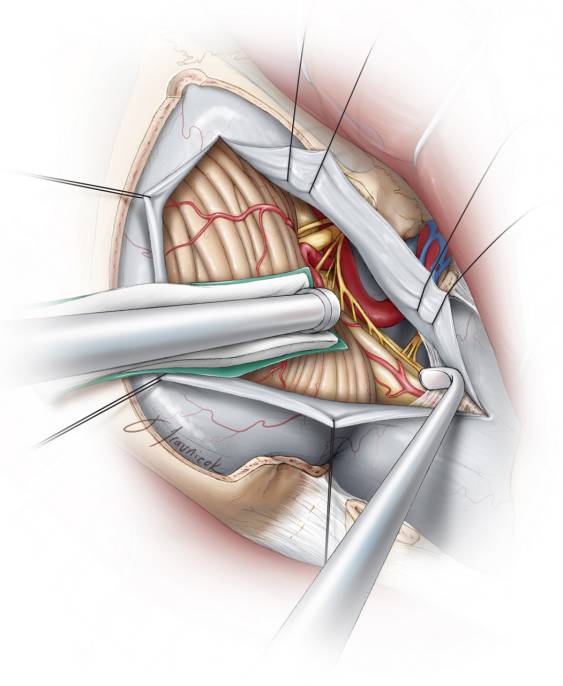

图6. 这一图片模拟手术视野和部分枕髁切除后的相关解剖。硬膜已经被移除。可以获得一个到达颅颈交界区腹侧硬膜的合理通道。位于这一区域的肿瘤会推移血管神经结构并拓展手术通道(图片感谢Rhoton教授授权)。

图13. 硬膜弧形剪开。剪开硬膜时小心避免损伤硬膜下血管神经结构,特别是硬膜下椎动脉及其分支,也包括可能被向后推移的脊副神经。肿瘤通常向外侧推移椎动脉颅内段近端。

图14. 术中图片显示通过最小的枕髁切除充分显露右前外侧的枕大孔区脑膜瘤(上图)。C1神经根和副神经的上1-2个脊神经根(上图-位于剪刀头端)可能会在显露这样的大肿瘤时被切断。沿肿瘤包膜后极向外侧移动副神经。最后的切除结果也被展示(下图)。在下图中你可以看见,这种有限枕髁切除理念的经髁入路足以到达颅颈交界区腹侧。

硬膜边缘用4-0缝线牵拉,并且术中应保持湿润,避免因显微镜灯光的高热而脱水;这有利于术后不透水缝合。缝线牵拉的针脚应沿骨缘分布(显露硬膜的最前方)来保证硬膜瓣最大程度远离手术视角。这一操作在椎动脉入硬膜处将其向外侧移位并远离术者的工作角度。